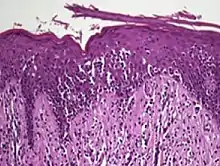

Histopathology of Pautrier microabscesses in cutaneous T cell lymphoma.

Pautrier's microabcesses are aggregates of four or more atypical lymphocytes arranged in the epidermis.[12] Pautrier microabcesses are characteristic of mycosis fungoides but are generally absent.